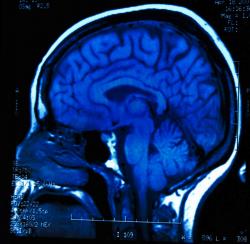

El Dr. John Kuo, director del Programa Integral de tumor cerebral en la UW Hospital de Clínicas y un cáncer de las células madre científica de la Facultad de Medicina y Salud Pública, está estudiando la posibilidad de utilizar CLR1404 para tratar el glioblastoma multiforme (GBM), una enfermedad mortal forma de cáncer cerebral, por atacar a las células madre de GBM.

En uno de la Asociación Americana para los carteles de la investigación del cáncer (# 3495), Kuo y Weichert describir cómo CLR1404 madre disminuye la actividad de células de glioblastoma, suprime el crecimiento de GBM y mejora la supervivencia de los animales.

Kuo implantaron células del glioma del tronco de los pacientes con GBM en ratones – y los tumores crecieron en sus cerebros. Cuando se inyecta otra forma de diagnóstico del agente, CLR1501, entró en las células madre y los iluminó. Incluso después de que los tumores se retiraron de los ratones y las células madre se aisló de nuevo, las células pluripotentes todavía brillaba, lo que indica la retención prolongada del agente.

«La infiltración de las células cancerosas en el cerebro normal adyacente limita la eficacia de la cirugía, la radioterapia y la quimioterapia se utilizan actualmente para el tratamiento de GBM», dice Kuo. «Retención específica de CLR1404 relacionados con los agentes en las células del cáncer sugiere su uso potencial como una terapia contra el cáncer a nivel celular – especialmente para las células invasoras que escapan a las terapias actuales -. Y reducir al mínimo el daño a las células normales del cerebro»